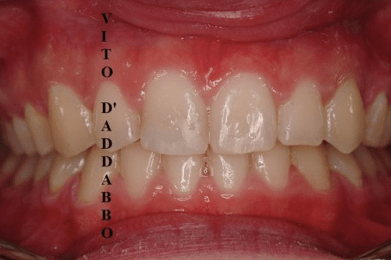

Non di rado accade che manchi in arcata il canino permanente superiore. Questo può essere dovuto a mancanza di spazio ma anche a problemi di eruzione del dente che si colloca lontano dalla propria sede. Nel caso di questa paziente, che presentava anche un grave morso coperto, il canino era dislocato palatalmente e molto distante dalla propria sede. Previo un piccolo intervento chirurgico è stato agganciato e portato in arcata.

dopo